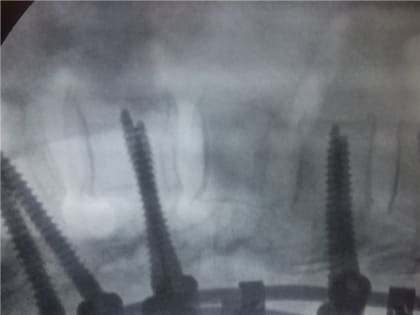

Клинический случай. Травма после катания на тюбинге.

Новый клинический случай у травматологов КМКБСМП. Молодая женщина была доставлена в больницу с травмой позвоночника, которую получила во время спуска с горы на тюбинге.

Красноярке после катания на «плюшке» пришлось винтами закреплять позвоночник

КРАСНОЯРСКИЙ КРАЙ, /НИА-КРАСНОЯРСК/. По словам медиков, порой спуски с горок заканчиваются инвалидностью.

Красноярка получила травму позвоночника во время катания на тюбинге

В Красноярске врачи БСМП прооперировали молодую женщину, которая получила серьезную травму позвоночника во время спуска с горы на тюбинге.